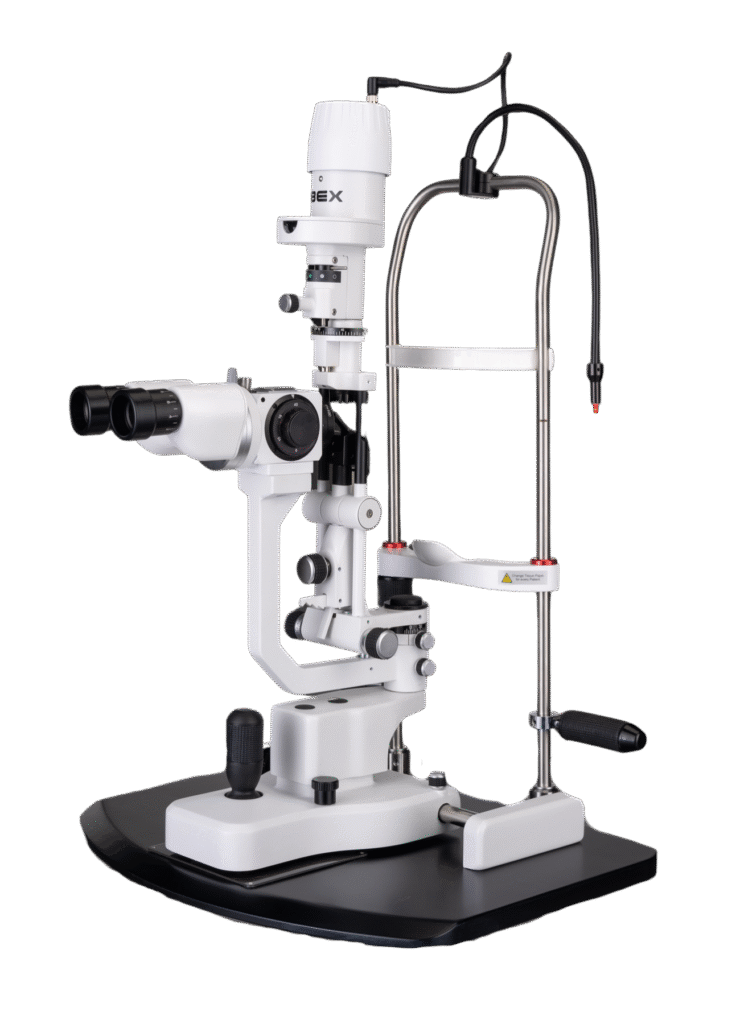

Opteon™ Slit Lamp Imaging + Meibography

Photos & Videos. Clinical Documentation. Patient Education. Reimbursement.

Illuminate your exams and transform patient engagement like never before. When patients see detailed images of their eyes, they gain a deeper understanding of their health and recognize the importance of compliance and follow-up care. Throughout development, our team saw firsthand the profound impact of imaging in the clinic—watching patients smile, express genuine appreciation, and embrace their health journey. That unforgettable experience remains the most rewarding part of our work.

Opteon was born and developed in the clinic, meticulously tested, and perfected through countless hours to ensure that it flows with your exam routine — delivering unmatched reliability and efficiency.

Pushing ahead, our imaging system includes our new, patent-pending Halo background light. Working with native slit lamp illumination, Halo delivers unparalleled clarity of the ocular adnexa. You’ll uncover details of the meibomian glands, acinar spaces, conjunctiva, lid margins, and lashes like never before.